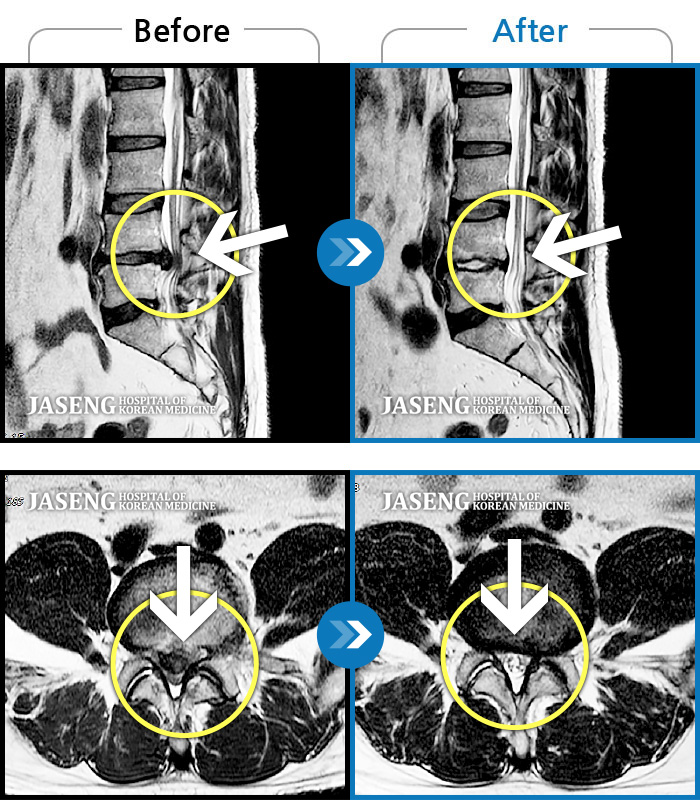

Before

After

환자에게 사전 동의를 받아 동일 조건에서 촬영되었습니다.

개인에 따라 치료 후 부작용이 발생할 수 있으니 의료진과 상담 후 치료를 진행하시기 바랍니다.

양측 허리부터 양측 골반까지 묵직하고 뻐근한 통증, 좌측 하지 외측으로 이어지는 통증